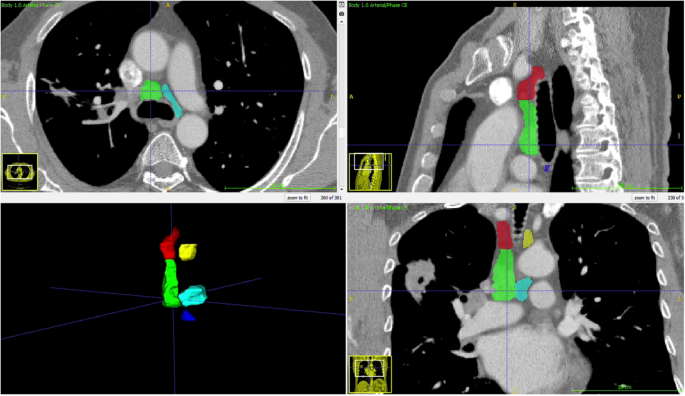

Thorax CTs were obtained in DICOM format and anonymized. A radiologist specializing in thoracic imaging measured the short and long axes of the largest lymph node at stations 2R, 2 L, 4R, 4 L, and 7 without clinical and pathological information. The radiologist also segmented these mediastinal N2 lymph node stations using ITK-Snap (version 3.8.0), and the segmentation files were stored as DICOM mask files in the NIFTI format (Fig. 2).

Development of machine learning algorithms

To develop the deep learning algorithm, we randomly divided the patients into three groups: 70% for training, 10% for validation, and 20% for testing. The raw DICOM data of thorax CT were adjusted to fit within a mediastinal window range of −140 to 260 Hounsfield Units, with regions outside the segmentation mask standardized to zero (Fig. 2). The algorithm was trained with only thoracic CT over 100 epochs using the ResNET50 architecture [6].